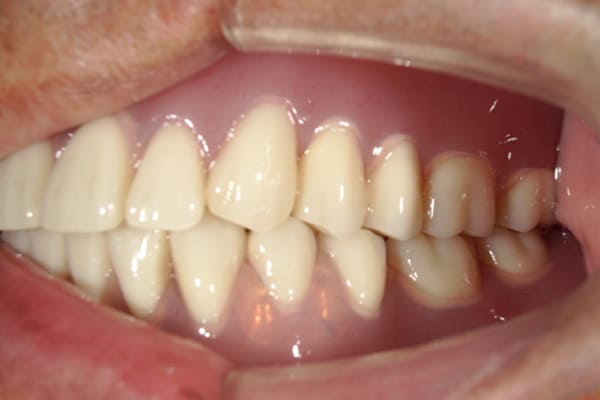

症例レポート[CASE.06]

下歯がぐらぐらで痛い、

咬めるようになりたい

- 性別・年齢

- 男性(70代)

- 主訴

- 下歯がぐらぐらで抜けそうで痛い、何でも咬めるようにしてほしい

- 治療

-

- 上顎精密金属床部分入れ歯

- 下顎精密金属床部分入れ歯

- 陶材焼付鋳造冠 4歯

- 磁性アタッチメント 1歯

- 治療期間

- 約6か月間

- 費用

- 上顎精密金属部分入れ歯:55万円

- 下顎精密金属部分入れ歯:77万円

(治療用義歯含、咬合平面等修正) - 陶材焼付鋳造冠:16.5万円×3歯

(ミリング加工) - 陶材焼付鋳造冠:14.3万円×1歯

(ミリングなし) - 磁性アタッチメント:11万円×1歯

(白金加金)

合計:157.3万円(税込)

奥歯がなくなり放置されていたため、前歯に負担がかかり、歯周病も併発されており歯がぐらぐらでお痛みも伴う状態でした。

可能な限り残せる歯は保存し虫歯治療を行い、どうしても残せないお痛みの歯のみ抜歯を行いました。

陶材焼着付鋳造冠 ミリングラべット加工

残りの歯が少ない場合は、入れ歯が動きやすく、またご自身の歯にも負担がかかるため、残りの歯の被せ物、入れ歯ともに、歯に負担がかかることを最小限にした特殊な加工を行い、歯を長持ちさせる設計としました。

上の入れ歯

下の入れ歯

上の入れ歯は、治療用入れ歯において、前方に違和感を訴えられていたため、違和感のない範囲を治療用入れ歯で決定し、最後の入れ歯に反映することで、上下ともに初めての入れ歯でしたが、違和感を感じることなくご使用になられることが可能になりました。

このように、お一人おひとり、お口の中の感覚は個人差が非常に大きいため、治療用の入れ歯でかみ合わせ、見た目、違和感、お痛みなど、あらゆる項目をチェックし、ご意見をお伺いし、ご相談のうえ最終的な入れ歯の設計を行い作製することで、その方に合った入れ歯が出来上がります。